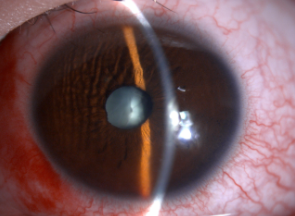

检查发现,王同学的晶体全白混浊,眼球穿通、巩膜裂伤,玻璃体崁顿在巩膜裂口处,随时有感染眼内炎症的风险。

术前晶状体全白混浊